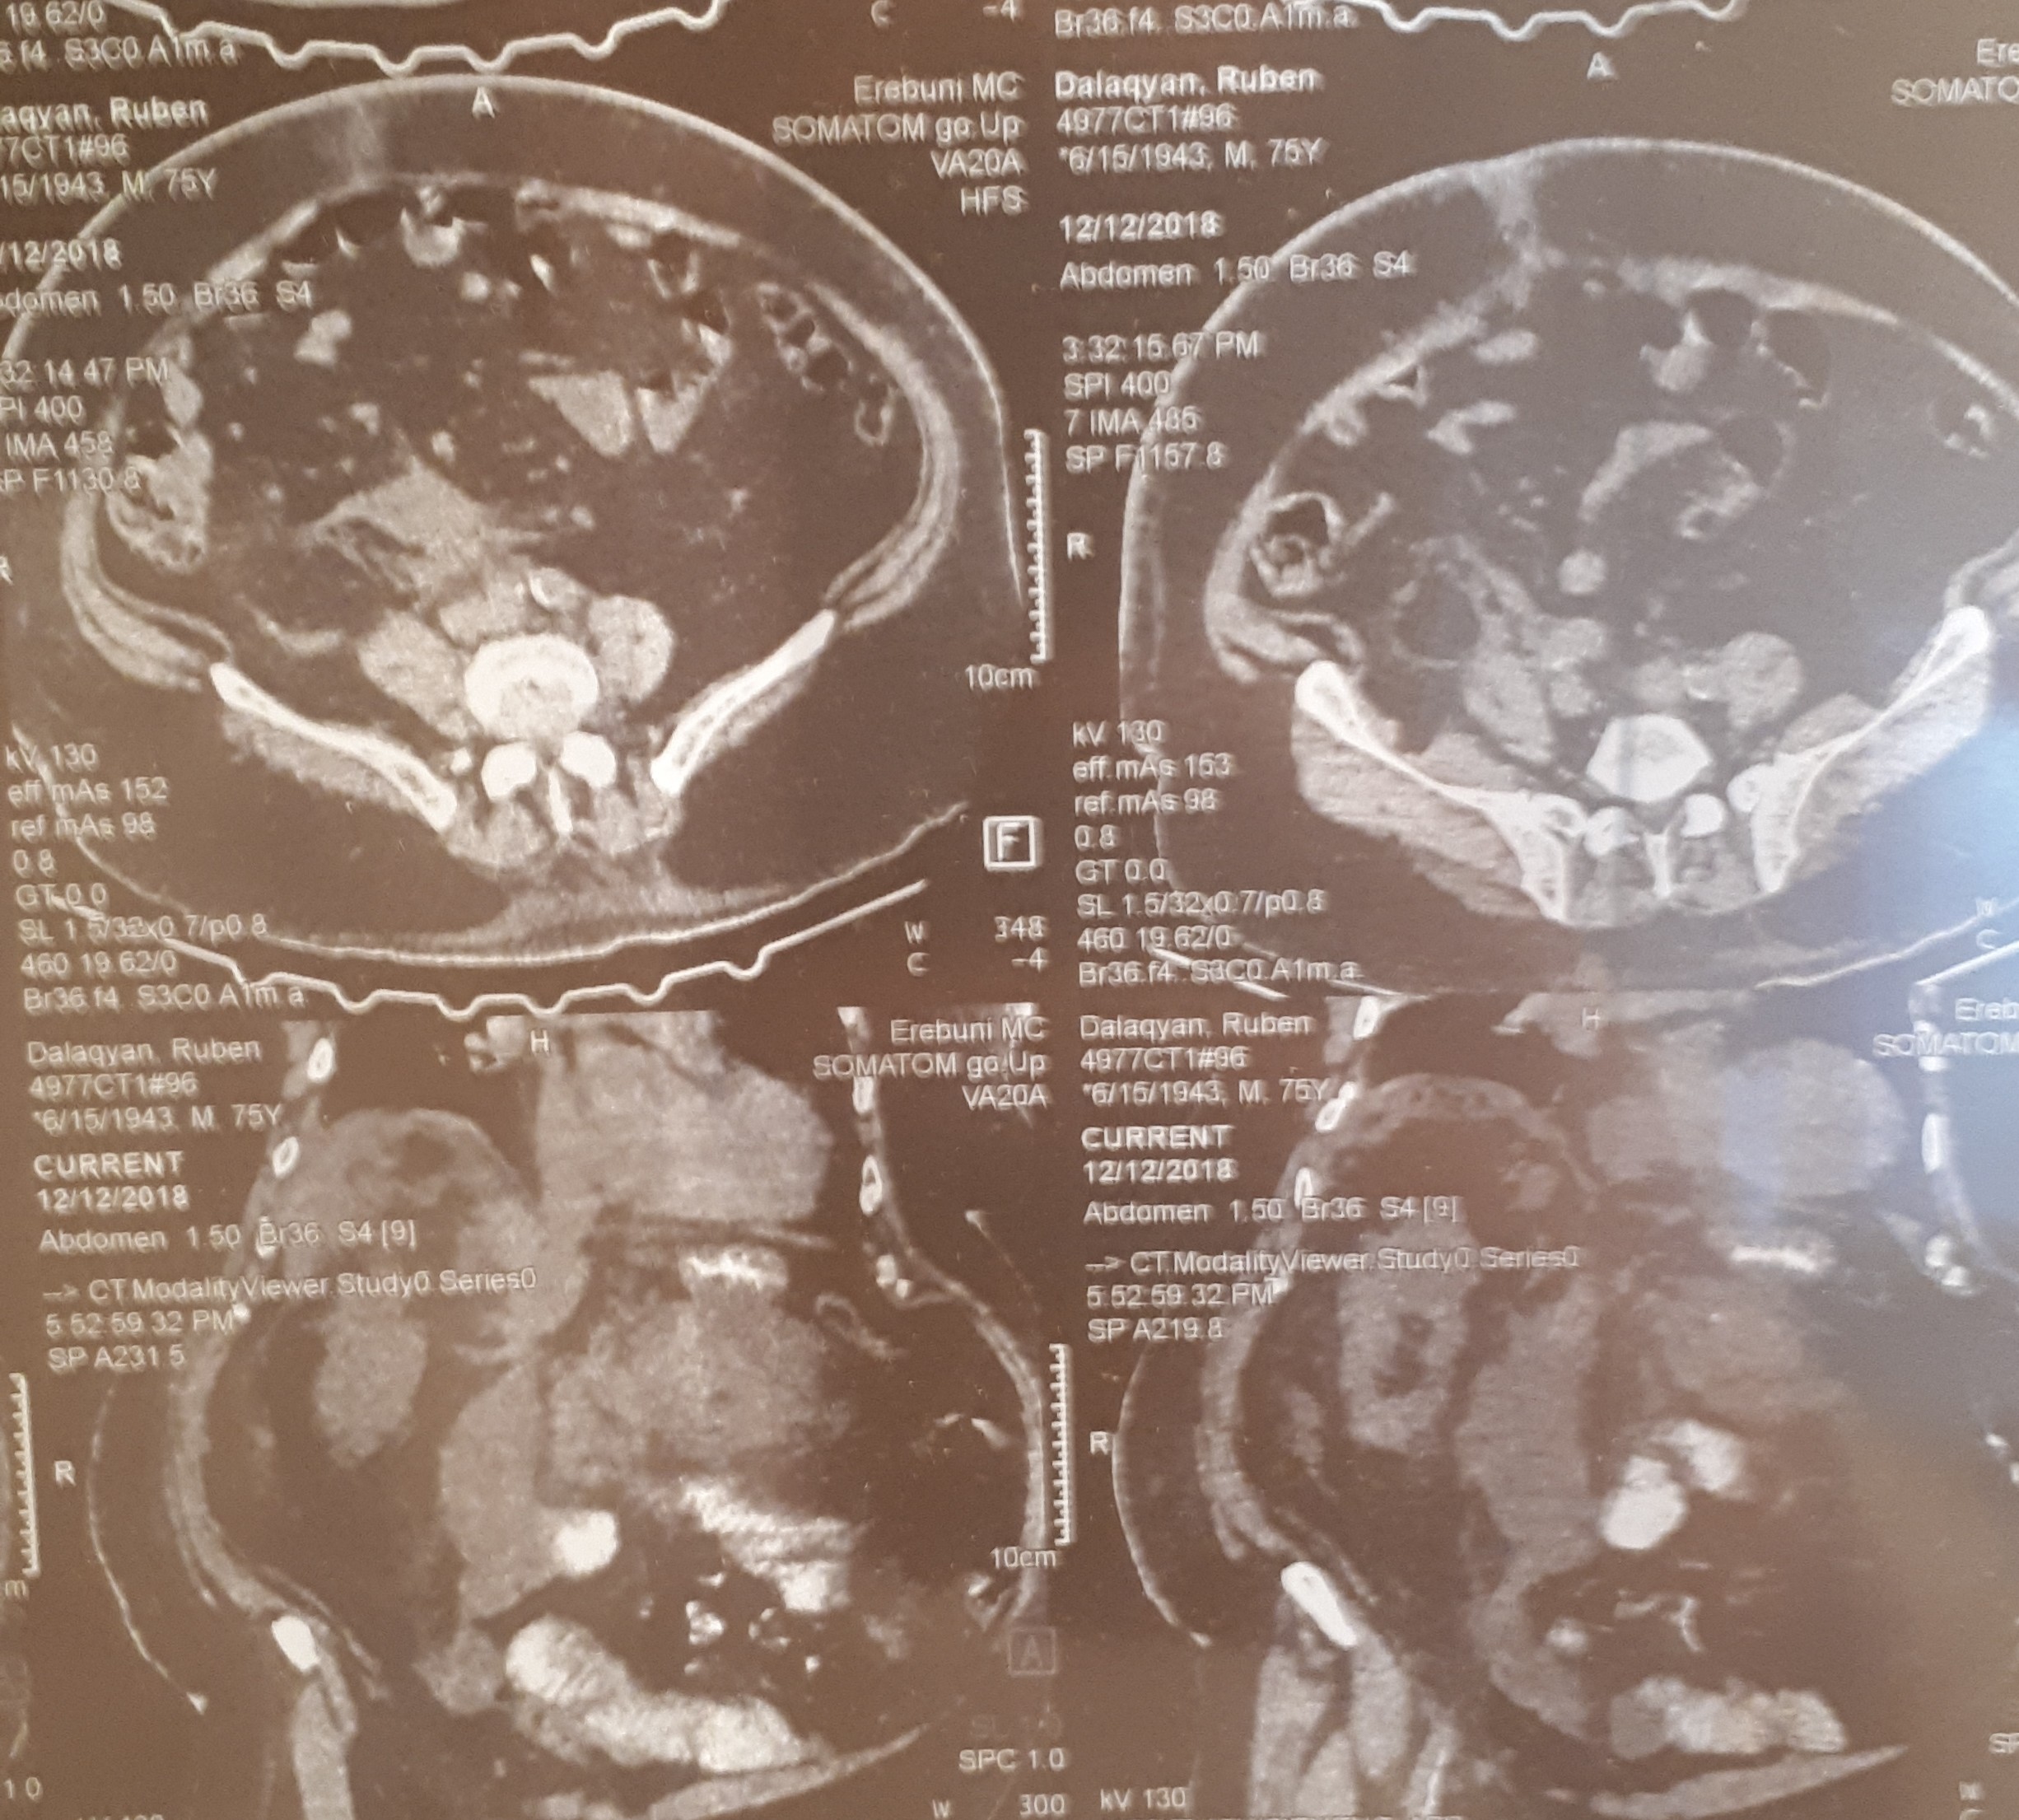

Օրինակ, ՈՒՁ հսկողության տակ դրենավորում կատարել: Առանց կտրվածքների, առանց ընդհանուր անզգայացման: Երեք մեծ թարախակույտ կար, որ հաջողությամբ հեռացրեցինք: Հիվանդը մի քանի օր անց տուն գնաց>>,- պատմում է բժիշկը:

տղամարդը եւ հիպերտենզիա ԱՓՇ-ում…Այս խնդիրների դեպքում բաց վիրահատությունը ուղղակի հակացուցված է: Արա Վարդանյանը ընտրել է այլ ճանապարհ: Առաջին հերթին՝ տեղային անզգայացման պայմաններումուլտրաձայնայինհսկողությամբ իրականացվել է հետորովայնամզային տարածության թարախակույտի դրենավորում, հաջորդ օրը կատարվել է ճարպոնային ծոցի դրենավորում: Սահմանվել է դինամիկ հսկողություն եւ կոնսերվատիվ թերապիա: Ինֆուզիոն, հակաբակտերիալ, սիմպտոմատիկ թերապիան շարունակվել է վիրաբուժական բաժանմունքում: Սրանով, սակայն, բուժումը չի ավարտվել: Մի քանի օր անց դրենավորվել է նաեւ աջից ենթադիաֆրագմալ տարածությունում առկա թարախակույտը: Հիվանդը ստոցիոնարում բուժումը շարունակել է եւս մի քանի օր եւ դուրս գրվել հիվանդանոցից բավարար վիճակում, ճարպոնային ծոցի եւ հետորովայնամզային տարածության գործող դրենաժներով: Նա, իհարկե, կշարունակի մնալբժշկի հսկողության տակ, բայց վերադարձել է նախկին կենսակերպին, ցավային զգացողություններ չունի: